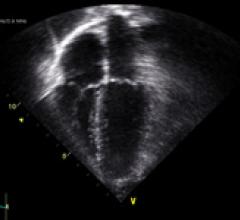

The 1.2 release of the ACUSON SC2000 volume imaging ultrasound system delivers nonstitched, real-time, full-volume ...

Since the introduction of cardiac ultrasound, investigators have sought to quantify cardiac function in three dimensions ...